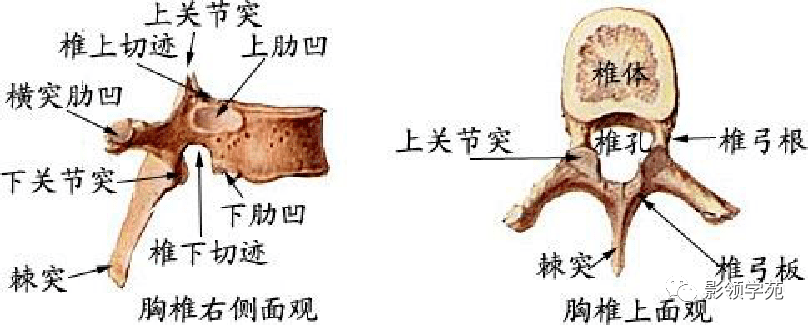

骨骼系统

骨骼系统